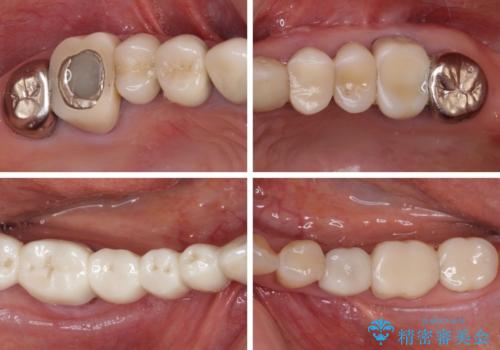

- 以前治療した歯が欠けたり、痛みを感じたりしているとのことで来院された患者様です。

アメリカ国内を転々としながら治療を行ったため治療跡がモザイク様で、クラウンが壊れていたり、抜歯が必要であったりしていました。

上下左右すべての奥歯に処置が必要であり、同時に行うと食事が取りにくくなってしまったり、手前の歯に負担がかかって初診時よりも状況が悪化したりする可能性があるため、片方ずつ処置を進めて行くこととしました。

下顎右側は骨造成を併用してインプラント治療を行い、その他の奥歯もインプラントや歯周外科処置を併用して補綴治療を進め、最後に前歯部の欠けてしまったセラミッククラウンを作り替えることとしました。